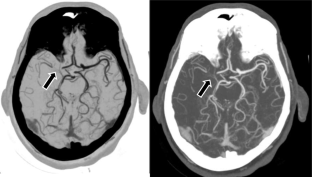

Fig. 1